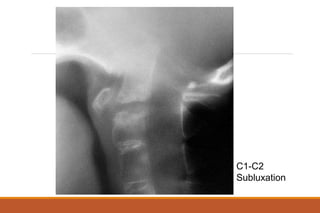

RHEUMATOID ARTHRITIS

X-rays

◦ The earliest changes occur in the wrist or feet and consist of soft

tissue swelling and juxta-articular demineralization.

◦ Later, diagnostic changes consisting of joint space narrowing and

erosions develop. The erosions are first seen at the ulnar styloid

and at the juxta-articular margin, where the bony surface is not

protected by cartilage.

◦ Diagnostic changes also occur in the cervical spine with C1-2

subluxation, but this can take several years to develop.

C1-C2

Subluxation